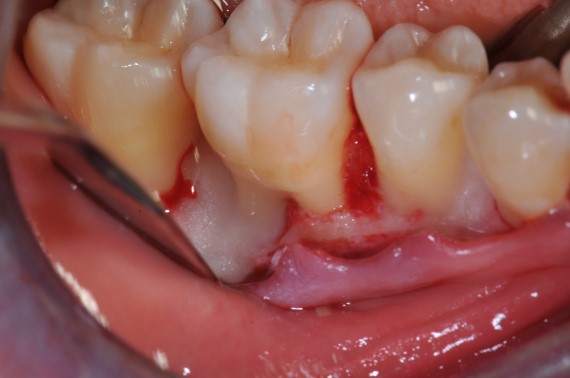

Radiographic view before periodontal regenerative therapy with Straumann® Emdogain®. A deep intrabony defect appeared mesially and distally on the left mandibular first premolar. Pre-surgical probing measured 8 mm. The defect morphology presented as well-contained.